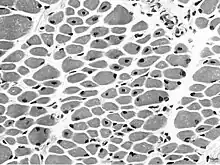

| Muscle biopsy from the quadriceps taken at 3 months of age from a girl with X-linked centronuclear ("myotubular") myopathy due to a mutation in the myotubularin (MTM1) gene and extremely skewed X-inactivation (H&E stain, transverse section). Note marked variability in fibre size, moderate increase in connective tissue and numerous central nuclei. | |

On examination of muscle biopsy material, the nuclear material is located predominantly in the center of the muscle cells, and is described as having any "myotubular" or "centronuclear" appearance. In terms of describing the muscle biopsy itself, "myotubular" or "centronuclear" are almost synonymous, and both terms point to the similar cellular-appearance among MTM and CNM. Thus, pathologists and treating physicians use those terms almost interchangeably, although researchers and clinicians are increasingly distinguishing between those phrases.

In general, a clinical myopathy and a muscle biopsy showing a centronuclear (nucleus in the center of the muscle cell) appearance would indicate a centronuclear myopathy (CNM). The most commonly diagnosed CNM is myotubular myopathy (MTM). However, muscle biopsy analysis alone cannot reliably distinguish myotubular myopathy from other forms of centronuclear myopathies, and thus genetic testing is required. Diagnostic workup is often coordinated by a treating neurologist. In the United States, care is often coordinated through clinics affiliated with the Muscular Dystrophy Association.